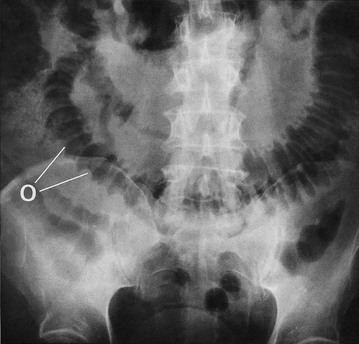

The most useful initial investigation is a plain supine abdominal X-ray (see Figs 19.2 to 19.4). The pattern and distribution of bowel gas often indicates the approximate site of obstruction. In small bowel obstruction, fluid levels may be visible on an erect or decubitus X-ray. Measuring the bowel diameter on X-ray gives the degree of distension. (See Box 19.1 for norms.)

Fig. 19.2 Radiological appearances of obstructed bowel

(a) Supine abdominal film in a man of 67 presenting with vomiting and abdominal distension. The film shows mid small bowel obstruction. Dilated small bowel fills the upper left quadrant and centre of the abdomen, and can be identified by the valvulae conniventes (plicae circulares P) which extend across the whole width of the lumen. The small bowel distal to the obstruction is collapsed and is not visible on this film. The large bowel is also collapsed, with faecal loading of the ascending colon (F) and only a small amount of gas in the sigmoid colon (S). Note also the metallic tip of the nasogastric (NG) tube and the incidental radiopaque gallstone.

(b) Erect film showing multiple loops of dilated small bowel and multiple fluid levels. The obstruction was caused by a small carcinoma of the medial wall of the caecum encroaching upon the ileal opening. Note: erect abdominal films are rarely taken nowadays